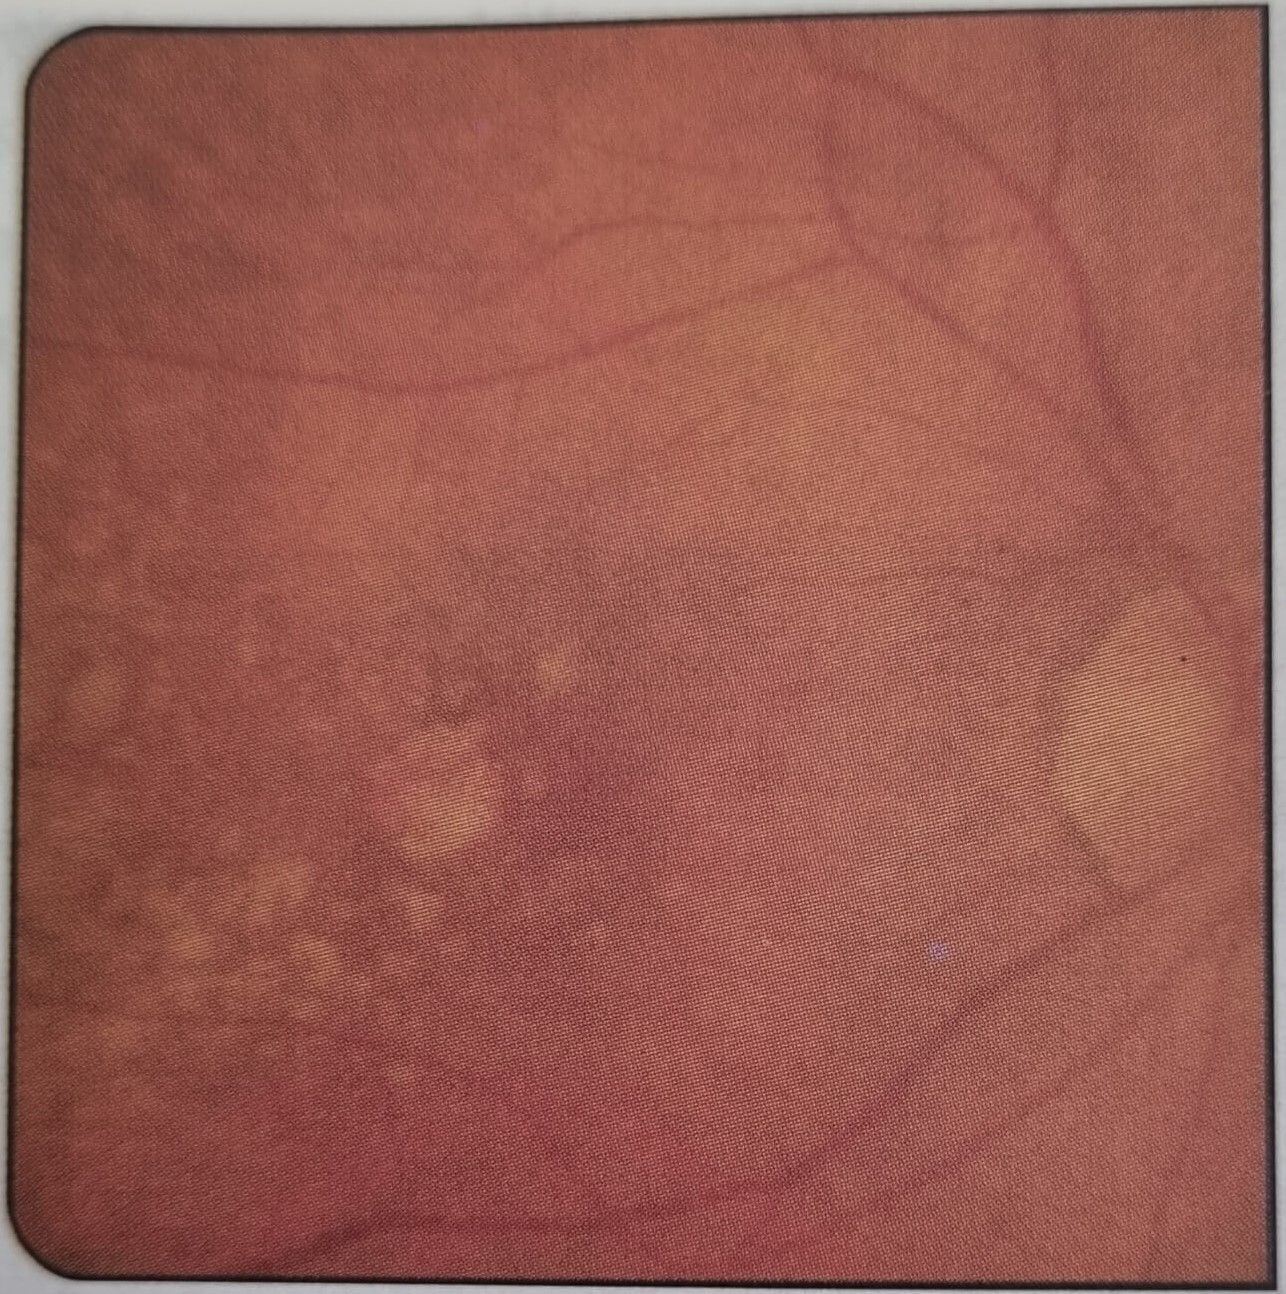

안구 망막의 중심에 있는 황반 부위에서 세포들이 손상되어 발생하는 질환으로, 시력 손실의 주요 원인 중 하나이며 주로 노화로 인해 발생하는 안구 질환입니다. 이 황반 부위에 있는 세포들은 시각 정보를 처리하고, 빛을 감지하여 뇌로 전달하는 역할을 합니다. 황반변성은 주로 50세 이상의 연령층에서 발생하며, 증상으로는 중앙 시력 손실, 뒷부분이 차단된 듯한 시야, 일관성 없는 색상 인식 등이 나타납니다. 황반은 망막의 중심에 위치하며, 망막 일부로 시각 정보를 처리하고 선명한 시야를 유지하는 역할을 합니다. 황반에는 중심부인 중심 황반과 주변을 둘러싼 주변 황반이 있으며, 중심 황반은 세밀한 세부 사항을 인식하는 데 중요한 역할을 합니다. 황반변성은 일반적으로 두 가지 형태로 나뉘는데 건성 황반변성은 가장 흔한 유형으로, 황반 조직의 자연적인 노화로 인해 발생합니다. 노화로 인해 황반 조직이 손상되고 변성되면서 중심 황반의 기능이 저하됩니다. 건성 황반변성은 천천히 진행되며, 시력 손실이 점진적으로 나타납니다. 습성 황반변성은 건성 황반변성보다 진행이 빠를 수 있으며, 혈관 형성과 연관된 변성 과정이 포함됩니다. 이 형태의 황반변성은 비타민과 미네랄 결핍, 고혈압, 흡연, 유전적 요인 등 다양한 요인과 관련될 수 있습니다. 황반변성의 초기 증상은 주로 중앙 시야 손실이며, 글자를 인식하거나 중앙 시야에서 물체를 인식하거나 세부 사항을 파악하는 데 어려움을 겪을 수 있습니다. 이는 글자를 읽을 때 난독증과 유사한 증상을 일으킬 수 있으며 모양이 흐려지거나 왜곡되는 것을 경험할 수도 있습니다. 주변 시야는 일반적으로 유지되며, 어두운 환경에서 더 큰 어려움을 겪을 수 있습니다. 질환이 진행되면 중앙 시야 손실이 더욱 심해지고, 심할 때는 시력이 심각하게 저하될 수 있습니다. 아직 완전히 치료할 수 없는 질환이지만 몇 가지 치료 옵션이 있으며, 진행을 늦추거나 증상을 완화 시킬 수 있습니다. 예를 들어, 일부 환자에게는 특정 비타민과 미네랄 보충제가 권장될 수 있으며, 심한 증상을 감소시키기 위해 주사 치료나 레이저 치료가 사용될 수도 있습니다. 일부 환자는 시력을 보조하기 위해 안경이나 확대 도구를 사용할 수도 있습니다. 황반변성은 초기에 증상을 감지하고 치료를 시작하는 것이 중요합니다. 완전히 치료되지 않지만, 조기 발견과 관리를 통해 진행을 늦출 수 있습니다. 정기적인 안과 검진이 중요하며, 의사의 지도 아래에서 치료 및 시력 보조 기기 사용을 고려해야 합니다.

노화성 황반변성은 나이가 들면서 발생하는 안구 질환으로, 황반 조직의 노화로 인한 변성이 주요 원인입니다. 일반적으로 50세 이상의 사람들에서 발생하며, 양쪽 눈 모두에 영향을 주며 시력 손실의 주요 원인 중 하나입니다. 초기에는 중앙 시야의 흐림이나 왜곡이 주로 나타나며, 일상생활에서 세밀한 작업이 어려워집니다. 점차 중앙 시야 손실이 심해지고, 뒷부분이 차단된 듯한 시야, 일관성 없는 색상 인식, 심할 때는 일상생활에 큰 제약을 가져옵니다. 노화성 황반변성은 황반 조직의 노화와 변성으로 인해 발생합니다. 노화성 황반변성은 일반적으로 건성 형태와 습성 형태로 구분됩니다.

가장 흔한 형태로, 황반 조직의 노화로 인해 발생합니다. 건성 형태에서는 황반 조직이 얇아지고 건조해지며, 중심 황반에 노화가 진행됩니다. 이에 따라 황반 조직의 세포와 혈관이 손상되며, 중앙 시야 손실이 발생하고, 세부 사항을 인식하는 능력이 저하됩니다. 시력 저하는 천천히 진행되며, 심한 경우 중앙 시야의 어둡고 흐린 지점이 형성될 수 있습니다.

혈관 형성과 연관된 변성 과정이 포함된 형태입니다. 이 형태에서는 새로운 혈관이 생성되거나 기존 혈관이 비정상적으로 성장하여 황반 조직을 침범할 수 있습니다. 이러한 혈관 변화로 인해 혈액이 누출되거나 축적되어 황반 조직이 손상되며, 중앙 시야 손실이 더 심해질 수 있습니다.